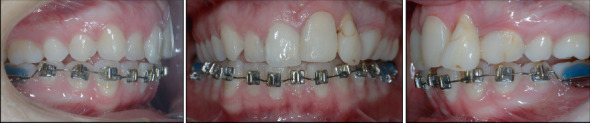

In this case report, we present the treatment of an adult patient who had experienced dental trauma resulting in the loss of one tooth and damage to two others. The patient was referred to our clinic 4 years after the accident, where a comprehensive examination revealed external root resorption and loss of supporting tissue. To address the patient's concerns, we developed an interdisciplinary treatment plan, which included orthodontic treatment to level the curve of Spee, reduce the deep bite, and extrude the affected teeth. After that, we extracted the damaged Teeth 2.1 and 2.2 due to their poor prognosis and replaced them with autotransplantation of Teeth 1.4 and 3.1. Before the procedure, both teeth underwent endodontic treatment, and 6 weeks later, they were built up to aesthetically and functionally replace the lost teeth. Additionally, postautotransplantation orthodontic treatment was conducted to close the donor site space and bring the autotransplanted teeth to an ideal position. The interdisciplinary approach and successful treatment of this case suggest that autotransplantation can be a valid option for restoring compromised teeth, especially in adult patients who require orthodontic treatment. In conclusion, autotransplantation offers multiple benefits, including preserving the natural dentition, avoiding the use of dental implants or prostheses, and achieving excellent aesthetic and functional results. Furthermore, this case underscores the importance of individualized treatment planning and collaboration among dental specialists to achieve optimal outcomes for patients.

Abstract Image